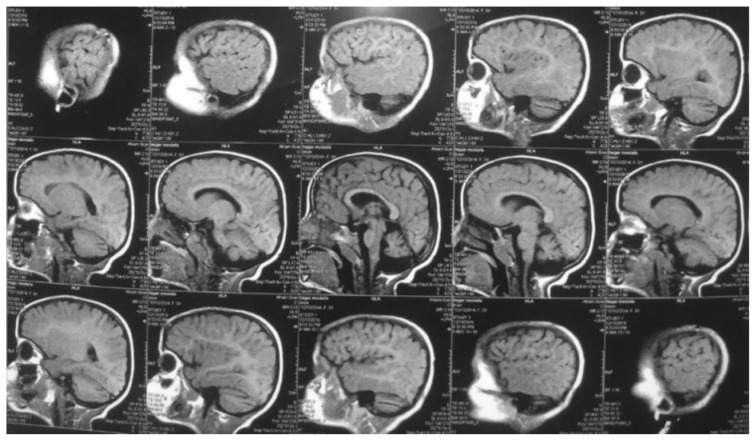

叶酸受体 1 基因(FOLR1)突变导致的脑叶酸转运缺陷,是由于叶酸通过血液:脉络膜:脑脊液(CSF)屏障的转运功能受损所致。这导致脑脊液中活性叶酸代谢物 5-甲基四氢叶酸含量偏低。我们报告了两名患有这种可治疗的脑叶酸转运缺乏症的儿童。八岁零九个月大的女婴发育迟缓,随后出现退步、癫痫发作和意向性震颤。经检查,患儿有小头畸形、全身肌张力低下、反射亢进、步态不稳和不协调等症状。脑部磁共振成像(MRI)显示脑室系统扩张和小脑萎缩。脑部计算机断层扫描(CT)显示脑部钙化。最后进行了全外显子测序,发现FOLR1基因第3外显子c.C382T p.R128W存在同型无义致病变异,确诊为脑叶酸缺乏症。12岁的女患儿自出生后就出现全面发育迟缓、肌阵挛性抽搐和认知能力退化。患儿全身肌张力低下,反射亢进。她的协调能力明显受到影响,并伴有意向性震颤和步态不平衡。脑部 CT 显示双侧基底节和脑室周围钙化,并伴有脑萎缩病变。脑部核磁共振成像显示小脑叶突出,伴有轻度脑萎缩病变。基因检测显示,在 FOLR1 C.327_328 delinsAC, p.Cys109Ter 中发现了一个同卵致病变体。两名患者开始肌肉注射亚叶酸,癫痫发作频率有所下降。然而,由于开始治疗较晚,他们的癫痫发作并没有完全停止。总之,如果患儿出现全面发育迟缓、顽固性肌阵挛性癫痫、共济失调并伴有神经影像学提示的小脑萎缩和脑钙化,则应怀疑其脑叶酸转运缺乏症。如果诊断较晚且治疗启动延迟,则对补充亚叶酸的反应是部分的。

Cerebral folate transport deficiency due to folate receptor 1 gene (FOLR1) gene mutation results from impaired folate transport across the blood: choroidplexus: cerebrospinal fluid (CSF) barrier. This leads to low CSF 5-methyltetrahydrofolate, the active folate metabolite. We are reporting two children with this treatable cerebral folate transport deficiency. Eight years and 9-month-old female presented with delayed milestones followed by regression, seizures, and intention tremors. On examination child had microcephaly, generalized hypotonia, hyperreflexia, unsteady gait, and incoordination. Magnetic resonance imaging (MRI) of brain revealed dilated ventricular system and cerebellar atrophy. Computed tomography (CT) of brain showed brain calcifications. Whole exome sequencing was finally performed, revealing homozygous nonsense pathogenic variant in FOLR1 gene in exon 3 c.C382T p.R128W, confirming the diagnosis of cerebral folate deficiency. Twelve-year-old female child presented with global developmental delay since birth, myoclonic jerks and cognitive regression. Child had generalized hypotonia and hyperreflexia. Her coordination was markedly affected with intention tremors andunbalanced gait. CT brain showed bilateral basal ganglia and periventricular calcifications with brain atrophic changes. MRI brain showed a prominent cerebellar folia with mild brain atrophic changes. Genetic testing showed a homozygous pathogenic variant was identified in FOLR1 C.327_328 delinsAC, p.Cys109Ter. Both patients were started on intramuscular folinic acid injections with a decrease in seizure frequency. However, their seizures did not stop completely due to late initiation of therapy. In conclusion, cerebral folate transport deficiency should be suspected in every child with global developmental delay, intractable myoclonic epilepsy, ataxia with neuroimaging suggesting cerebellar atrophy and brain calcifications. Response to folinic acid supplementation is partial if diagnosed late and treatment initiation is delayed.